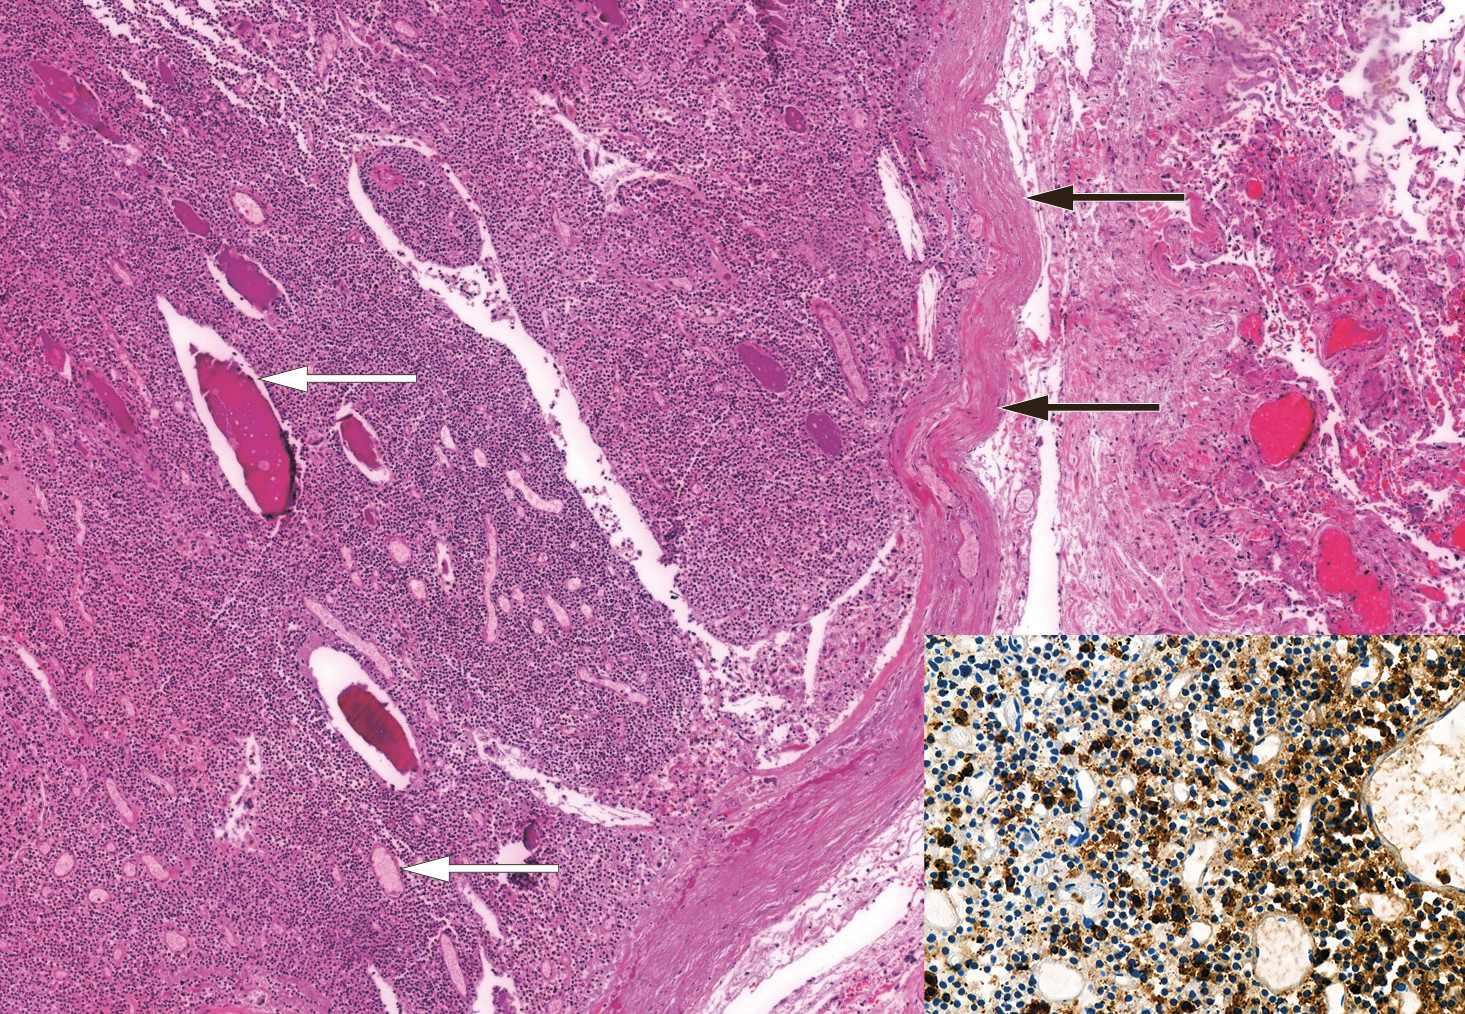

Det ble utført obduksjon. Svarende til pankreas' anatomiske lokalisasjon og videre under diafragma på venstre side var det rikelig gråbrunt nekrotisk materiale. Det ble påvist sparsomt med bevart pankreasvev med spredte hvite stearinflekker som ved pankreatitt, med overgang til nekrotisk område forenlig med utbredt nekrotiserende pankreatitt. Medialt i venstre lunges underlapp subpleuralt var det en 16 mm stor velavgrenset svulst. Svulsten var rødbrun med fast konsistens og homogen snittflate. Ved mikroskopisk undersøkelse var den kapselkledd og bestod av små celler voksende i flak, med moderat mengde cytoplasma og runde kjerner uten tydelig nukleol (figur 4). Det var svært få mitoser og ingen sikker nekrose. Cellene i svulstvevet var positive for de nevroendokrine markørene CD56, synaptofysin og kromogranin A, mens tilstøtende lungevev var negativt.

Immunhistokjemisk farging for ACTH viste tydelig positivitet i cytoplasma i svulstcellene. Betydningen av proliferasjonsmarkøren Ki67 i obduksjonsmaterialet er usikker, men det ble bemerket svært lav Ki67 i svulstvevet mens det forelå spredt positivitet i tilstøtende lungevev, hovedsakelig i områder med kronisk betennelse. Det histologiske bildet passet med lavgradig nevroendokrin tumor i lunge, såkalt karsinoid, hvor funn av < 2 mitoser per 2 mm2, Ki67 ≤ 5 % og fravær av nekrose er forenlig med typisk karsinoid (3). For øvrig var binyrene litt store og preget av autolyse, men med bevart overordnet arkitektur. Hypofysen var upåfallende og uten holdepunkt for adenom.

Samlet var klinisk utredning og funn ved obduksjonen forenlig med Cushings syndrom forårsaket av ektopisk ACTH-produksjon fra karsinoid tumor i lunge. Det kliniske forløpet kunne passe med syklisk Cushings syndrom (4).